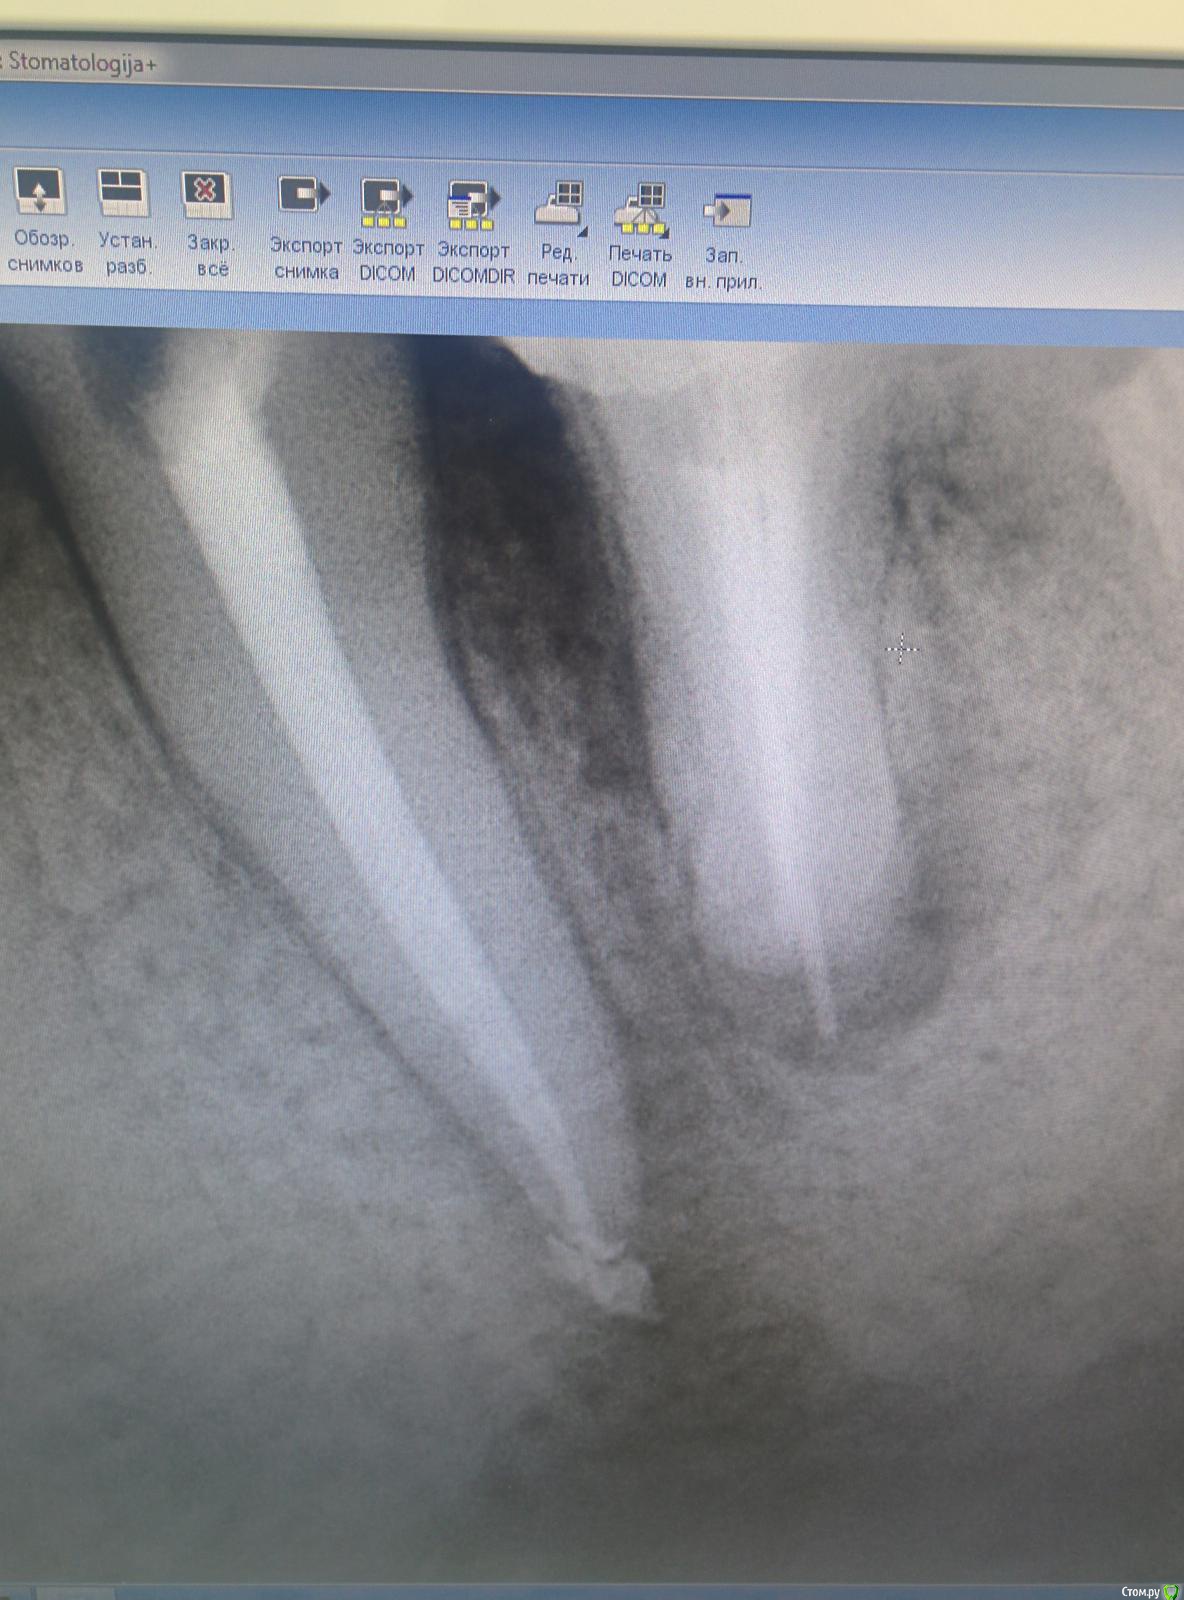

mermaid Опубликовано 18 февраля, 2015 Поделиться Опубликовано 18 февраля, 2015 Добрый вечер!ситуация следующая пол года назад в клинику пришла пациента с отеком на нижней челюсти слева.делаем снимоксразу думала 36,но перкуссия +только в 35,открыли,промыли(эдта+хлорка) ,Са,через 2 недели закрыла постоянно акросил+шрифты Через пол года рецидив,снова отек(36 лечить пациентка всячески отказывалась,уж очень не хотела снимать мостик)и снова перкуссия исключительно на 35 положительна,распломбировала,нашла подобие 2ого канала,долго мыла эдта,тёплой хлоркой,са.через 2 недели в день пломбировки снова отек....и опять мыла в коффере около часа,са.ещё через 2 недели пломбировка Поставили пломбочку...а через неделю звонок...снова отекли!!разобрали все-таки 36(резорцин более 20 лет,10 лет назад попытка перелечивания,костный карман..перфо в дистальном..хирург чешет лапки)Пациентка устала и готова к удалению(((где косяк???p.s.зондирование по по маргинальному краю в поисках трещины проводила,но провалов нетP.s.ещё смущает наличие плотного костного выбухания в области 35 Ссылка на комментарий